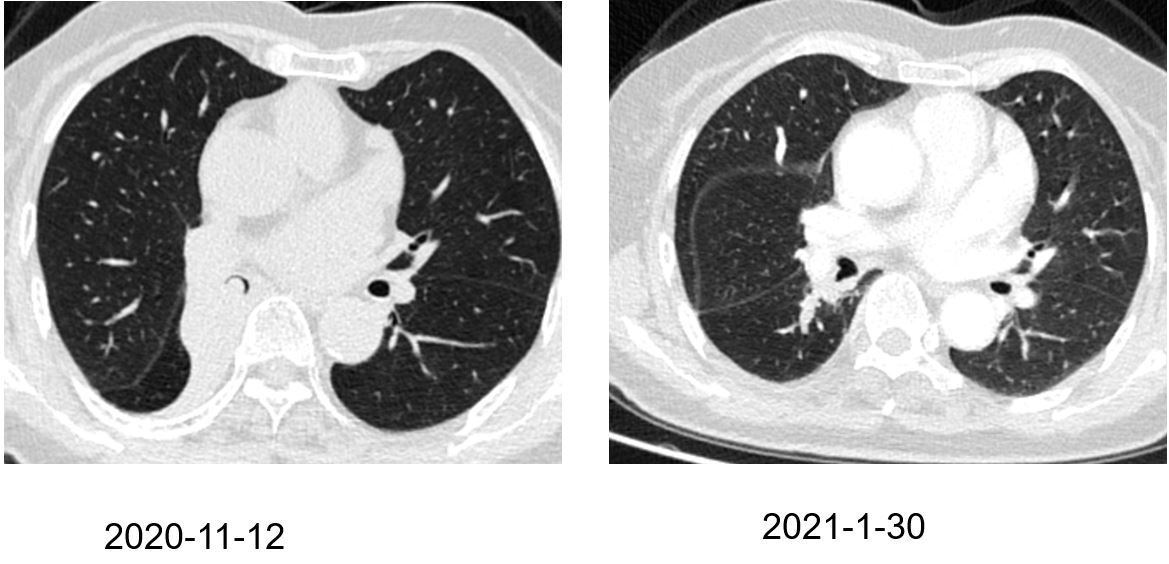

?0? 胸腔莫名“淹水” 憋坏爹爹的肺,医生变“肺”为宝成功治水(通讯员 张全录)胸腔莫名积水,长期“清波荡漾”,处在胸腔内的肺,伸缩空间被压缩大半,72岁患者林师傅(化姓)憋闷多年,多方就医未果。昨天,在武汉市肺科医院,医生巧用“移花接木”术,让肺客串“创可贴”,成功堵住了位于胸壁上的大片挂壁“泉眼”。林师傅感叹,憋闷多年,幸福一下来...